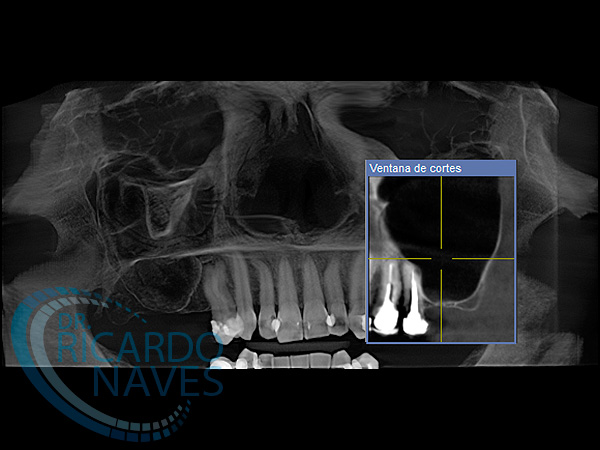

Elevación de seno maxilar técnica de ventana lateral.

Antes y después de elevación de seno bilateral. 5 meses de evolución. Obsérvese la cantidad de hueso que podemos ganar  en estas verdaderas cajas biológicas.